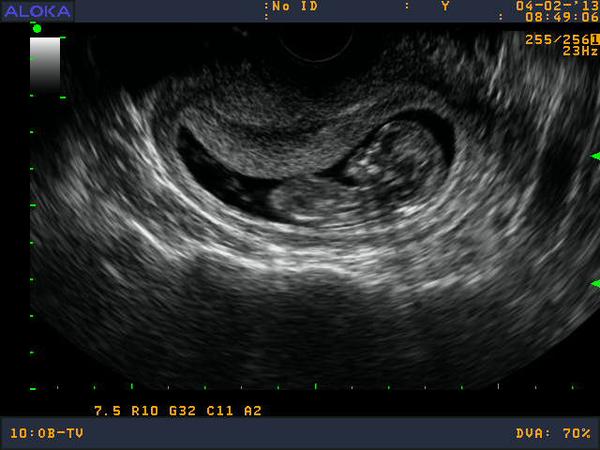

Neviete náhodou, či tie soná čo nám robia nie sú pre dieťatko škodlivé?! Ako často sa môže robiť a pod.?!

Či to nevyžaruje nejaké žiarenie, čo škodí, by ma zaujímalo.

@rybca Lebo mne lekár pri každej návšteve robí sono, plus mám za sebou to špeciálne sono, zasa ma čaká v 20tt, tak som dostala pochybnosti, či to neškodí bábu. Aj čítam na nete, ale jeden napíše tak, druhý tak, tak som z toho jeleň. A lekár asi pravdu nepovie, keď má z toho prachy.